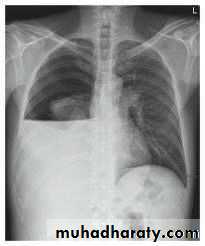

1. CXR 2. CT scan

1) well defined circular or oval homogenous opacity

thoracic surgery

2) perivesicular pneumocyst or signet ring sign